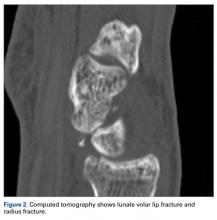

Later, however, the hand surgery team evaluated the radiograph as well as computed tomography (CT) scans and found a translunate, transradial, transtriquetral, transtrapezoid perilunate dislocation of the wrist with multiple metacarpal neck fractures ( Figures 1-5 ).The next day, with the patient under general anesthesia, an attempt to reduce the perilunate dislocation by manipulation was unsuccessful. Open reduction and internal fixation (ORIF) were performed through a dorsal approach; the perilunate dislocation was reduced and stabilized with lunocapitate 1.2-mm Kirschner wire (K-wire). The scapholunate and lunotriquetral ligaments were found to be intact, and the significantly displaced triquetral fracture was treated with internal fixation involving 2 minifragment screws ( Figure 6 ).

Our patient’s associated multiple metacarpal neck fractures can be explained by the peculiar double-impact injury with initial axial loading across the hyperextended metacarpophalangeal joint, followed by axial loading across the hyperextended and ulnar-deviated wrist, causing greater arc perilunate fracture-dislocation. The mechanism of lunate injury in this case seems to be longitudinal impaction of the capitate shearing against the volar lunate in the axial plane causing a volar lip fracture (Teisen type I), and this may be accentuated by tension in the volar radiolunate ligament. 6,7 Associated triquetral fracture in perilunate dislocation is well described in the literature. 6 However, the trapezoid fracture in our case implies a very atypical pattern of force transmission with the arc probably passing more distally through the trapezoid laterally and the triquetrum medially.